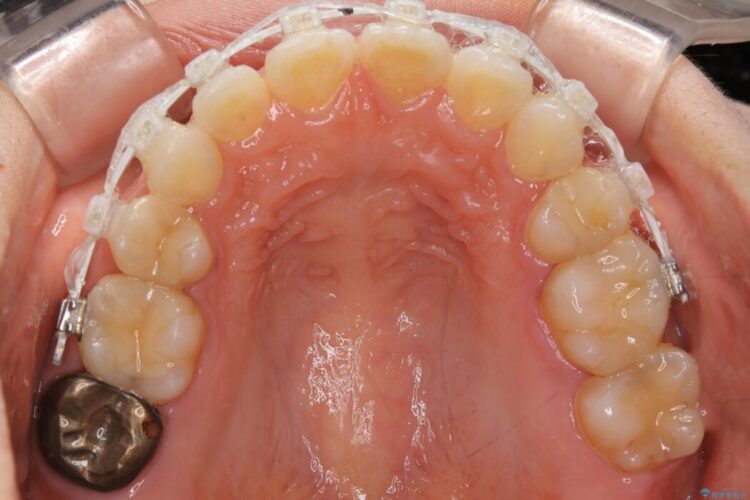

【20代女性】矯正治療後の後戻り

- 患者様:20代女性

- 治療期間:1年

- 矯正装置:審美装置

- 概算治療費:66万円

抜歯矯正後の後戻りについてご相談にいらした患者様です、

いつもでしたらマウスピース矯正をおすすめするのですが、自己管理の煩わしさから、目立たないワイヤー装置にて矯正治療を行うこととしました。

後戻りの程度としては軽度なので、治療期間としては短く終えることが出来ました。

前歯の正中線も改善され大変満足していただきました。